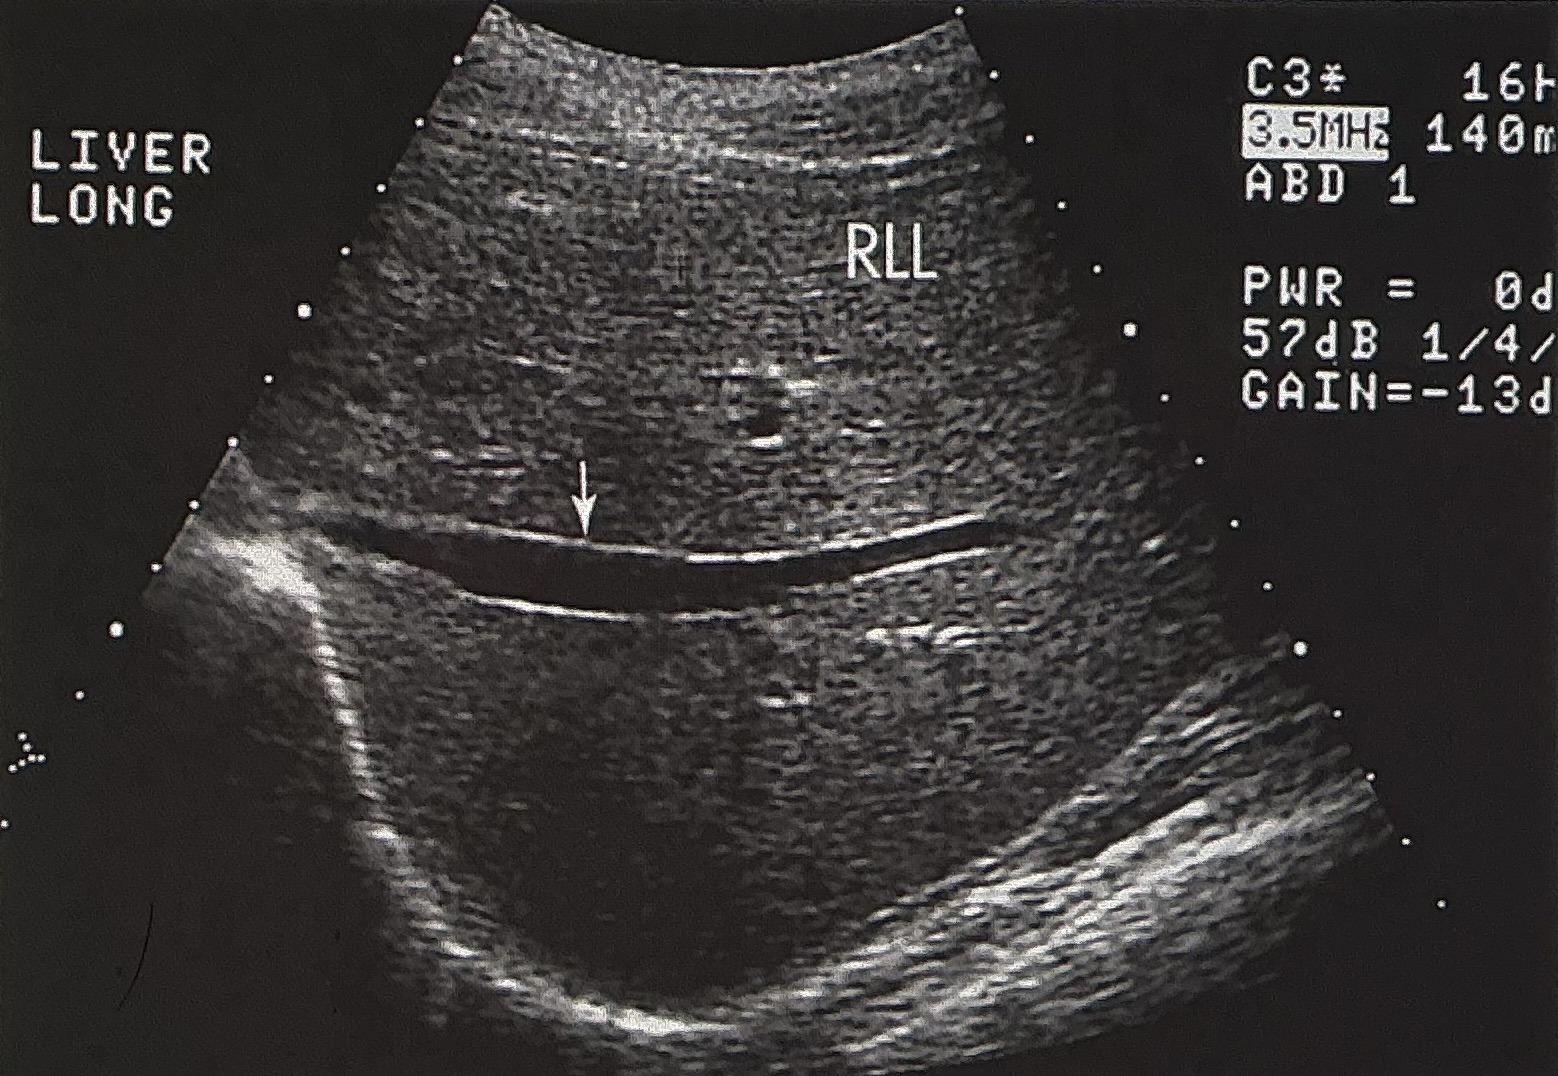

Name and describe this image: Include scan plane, and name the structure identified by the white arrow.

longitudinal image of the right lobe of the liver

the structure is the right portal vein

liver tissue appears homogenous throughout and is hyperechoic to the vessel’s lumen. The vessel is anechoic, with echogenic borders.